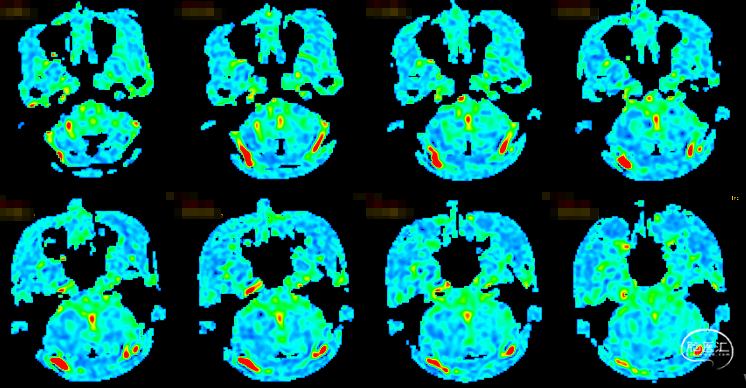

ASL示:双侧小脑半球、脑干低灌注改变。